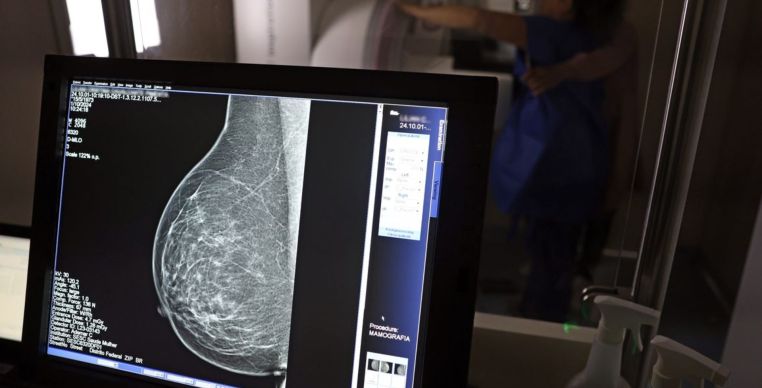

O Ministério da Saúde passou a recomendar que mulheres de 40 a 49 anos façam mamografia pelo SUS, mesmo sem sinais ou sintomas de câncer de mama. A mudança, anunciada nesta terça-feira (23), baseia-se em dados que apontam que 23% dos casos da doença ocorrem nessa faixa etária, na qual a detecção precoce aumenta as chances de cura. Até então, o exame era indicado a partir dos 50 anos.

Dados oficiais indicam que, em 2024, 30% das mamografias do SUS foram realizadas em mulheres com menos de 50 anos, somando mais de 1 milhão de exames. Outra novidade é a ampliação da faixa etária do rastreamento ativo, que passa de 69 para 74 anos. O rastreamento ativo é quando a mamografia preventiva é solicitada a cada dois anos. A medida é fundamental, pois quase 60% dos casos de câncer de mama se concentram entre 50 e 74 anos.